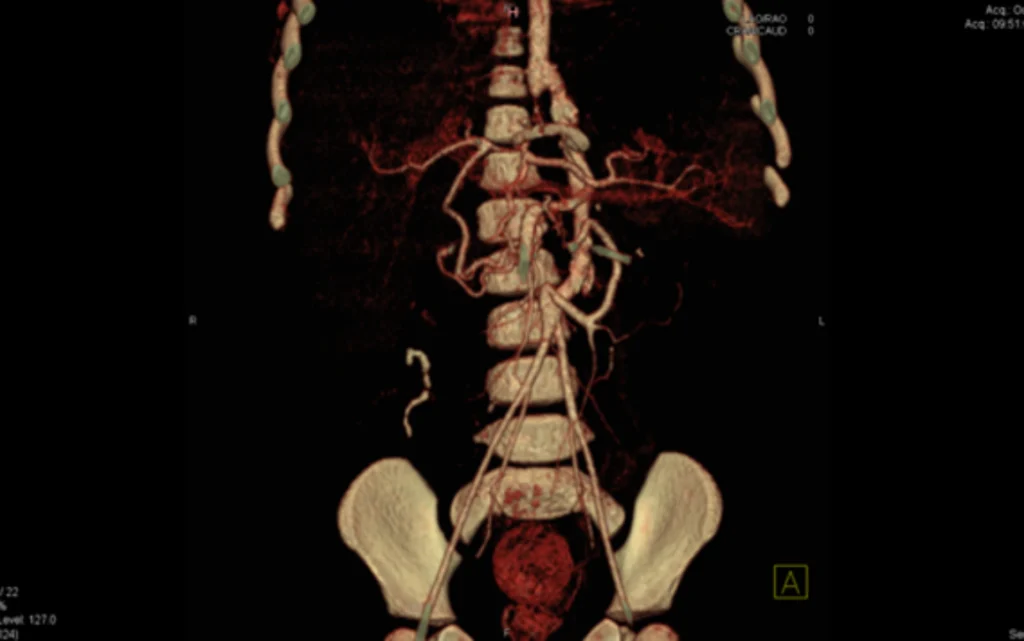

The pre-operative use of 3-D modelling of the vascular anatomy in children that have malformations of their vena cava and aorta.

Arterial anastomosis window

Picture of venous and aorta malformations and classification.

A4:V4 malformation